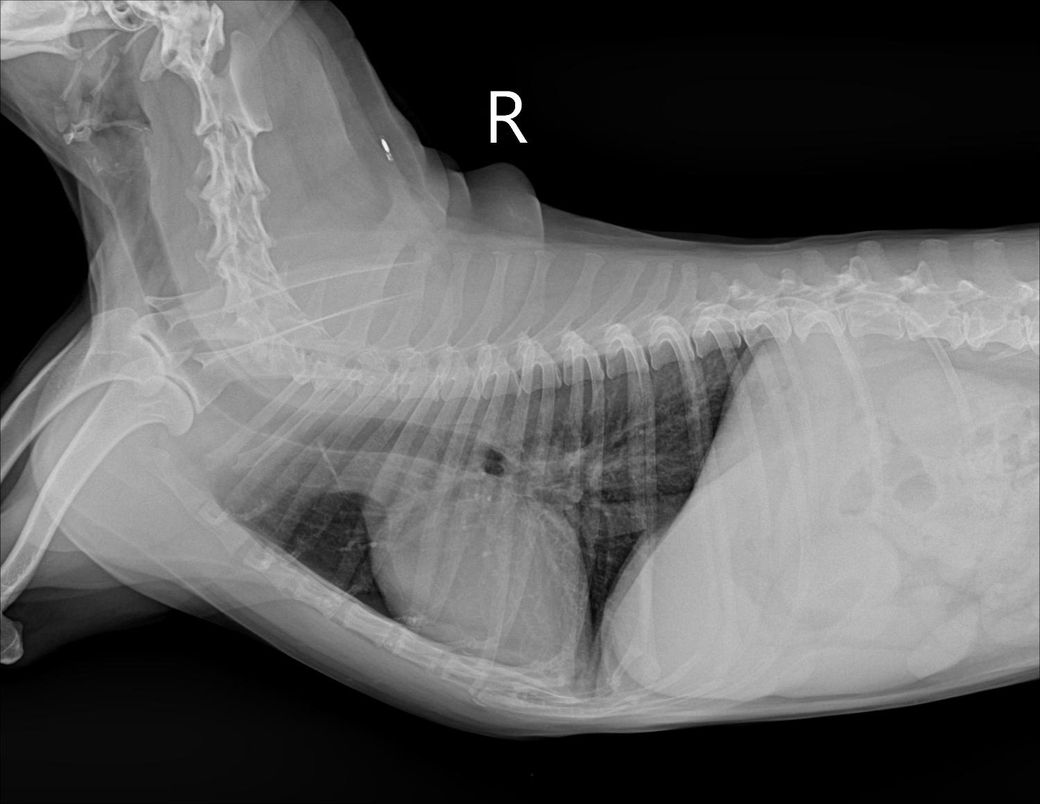

간크기 작다고 하는데 어디를봐야 작은걸 알수있을까요?? 정말 간이 작은 편인건도 궁금합니다!!

믹스(중성화o), 몸무게9.3kg 입니다